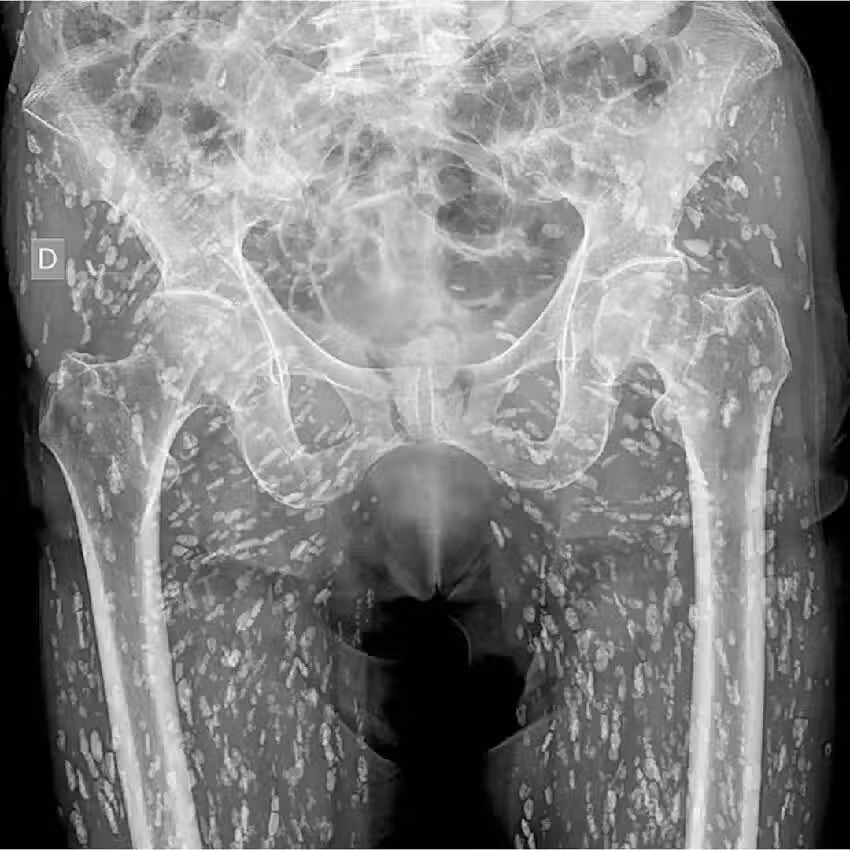

根據媒體《Khaosod》的報導,一名泰國網友「Ai Jaeo Mueang Chan」在臉書分享,自己過去在擔任X光助理時,一名婦人到診所拍攝從髖部到腿部的X光,結果影像一出來布滿詭異陰影,放射科醫師一看,指出這些白點其實全是寄生蟲!他直言,當時的畫面就像下圖: